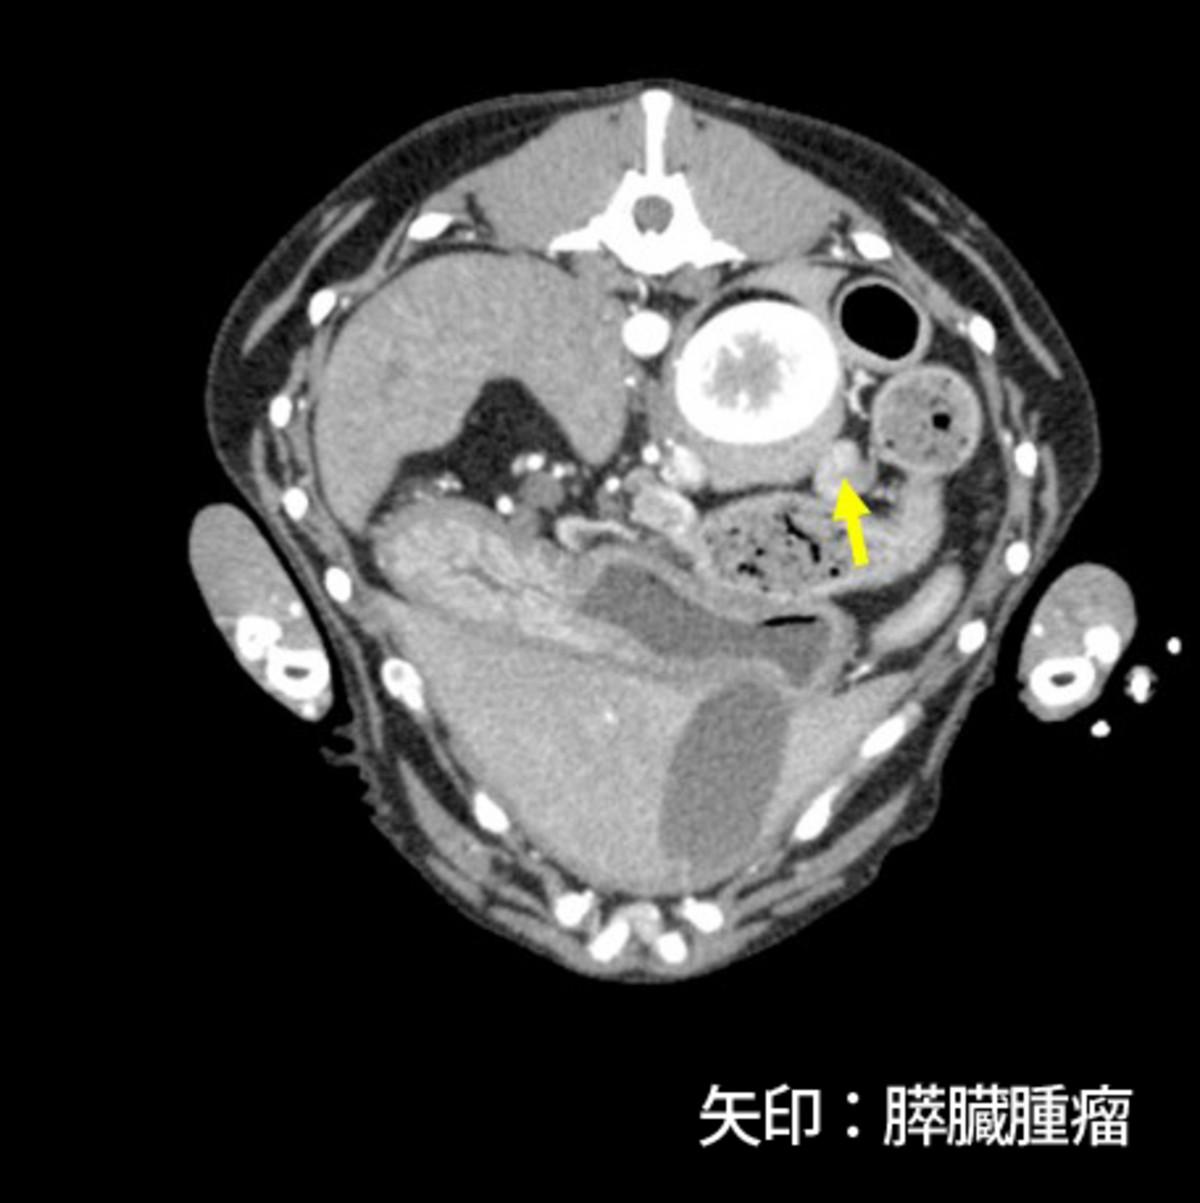

症例はバセンジー、去勢雄、11歳8ヵ月齢、10.5kgです。当院初診の一月前にふらつきを認め近医を受診し、低血糖(38mg/dL)、インスリン高値が認められたためインスリノーマと仮診断され、少量頻回の食事と糖液の投与により一般状態を維持していました。初診時の血液検査では血糖値は正常であり、CT検査にて膵臓右葉尾側に腫瘤(15×10×10mm)、肝臓外側左葉の腫瘤(5mm大×2)、肝門リンパ節腫大(12×10×6mm、15×9×7mm)が認められました(図1)。肝臓への転移が疑われるため、根治は難しい可能性が高いものの臨床症状およびQOLの改善を目的とした手術が予定されました。

図1.CT検査にて膵臓腫瘤(図1-1)、肝門リンパ節腫大(図1-2、1-3)を認めた